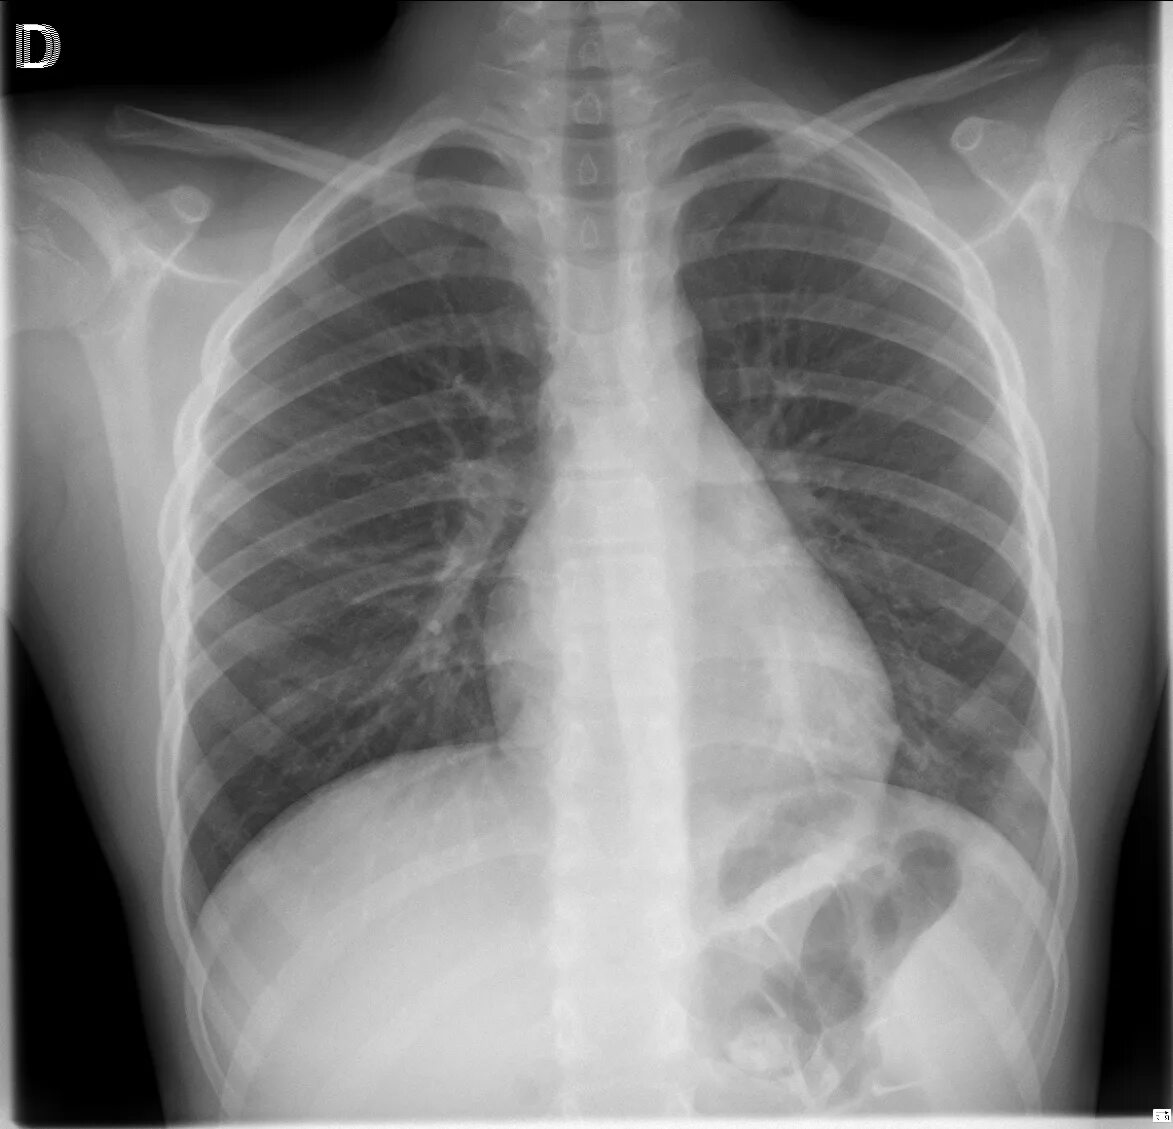

Рак легких 1